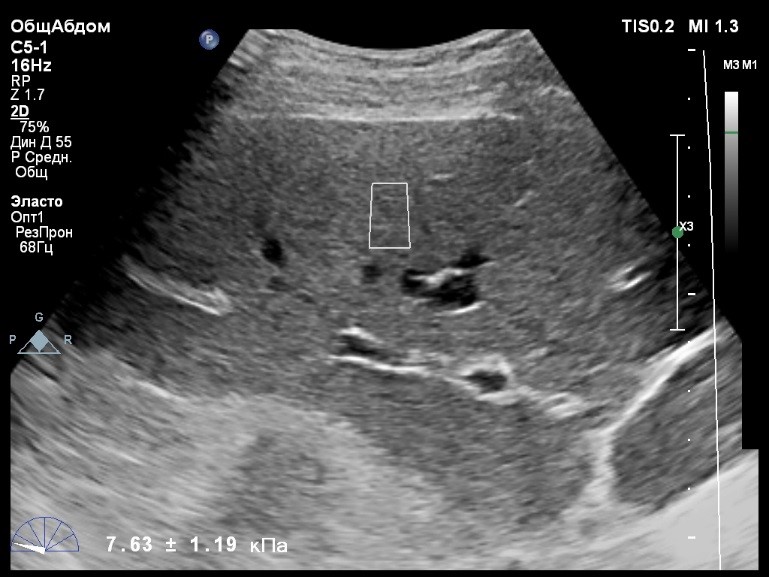

Пациент обратился к доктору с направлением на исследование степени жесткости печени в июне 2017 года. Из истории болезни, пациент страдает Гепатитом С с 2015 года. Лечение не получал. В апреле 2016 года, с помощью транзиентной эластографии была установлена медиана жесткости печени 5,8 kPA (4,4-7,7). На момент настоящего исследования, пациент не принимал пищу на протяжении 4 часов, АСТ, АЛТ не превышают патологических значений. Для оценки жесткости была выбрана технология компании Philips ElastPQ (точечная эластография) и прибор компании Philips Epiq 7 Исследование было проведено в соответствии с клиническими рекомендациями для ультразвуковых приборов компании Philips. В результате исследования были получены следующие результаты:

| 1 [4.94] kPa | 2 [7.09] kPa | 3 [7.13] kPa |

| 4 [4.74] kPa | 5 [5.17] kPa | 6 [7.78] kPa |

| 7 [6.19] kPa | 8 [7.63] kPa | 9 [4.64] kPa |

| 10 [6.18] kPa | 11 [4.49] kPa | 12 [4.54] kPa |

| 13 [6.08] kPa | | |

Стандартное Отклонение [1.17] kPa Медиана Жесткости [6.08] kPa Фактор Качества IQR/Med 9%

Зона интереса расположена на более чем на один сантиметр глубже капсулы, параллельно ходу луча, в середине изображения, в участке печени лишенном артефактов.

Капсула видна как белая линия перпендикулярная ходу ультразвукового луча, исследования производятся приблизительно в одном и том же сегменте печени.

Стандартное отклонение (0,96 kPA) не превышает 30 процентов от полученного значения (4,54 kPA).

Зона интереса расположена вне крупных сосудов.

Для интерпретации полученных клинических данных были использованы Рекомендации по проведению эластографии сдвиговой волной для оценки жесткости печени при использовании ультразвуковых аппаратов компании Филипс с примером протокола. Анамнез основного заболевания пациента достаточно короткий и показатели жесткости печени, полученные в 2016 свидетельствуют об отсутствии значимых фиброзных изменений. Однако, в течении всего времени пациент не получал специфического лечения. Данный факт является показанием для динамического наблюдения и оценки жесткости печени. Подготовка пациента соответствовала проводимому исследованию. Представленные слайды проведенного исследования свидетельствуют о правильном техническом исполнении проб, что позволяет заключиться о достоверности полученных измерений. Таким образом, учитывая полученную медиану жесткости на уровне 6.08 кРа (4.49 – 7.78 kPa) и уровень стандартных отклонений не превышающих 30%, полагаю, что уровень степени фиброза соответствует стадии F 0-1. Заведующий отделением УЗД МЦ «Асклепий», Глушенко Д. Е.